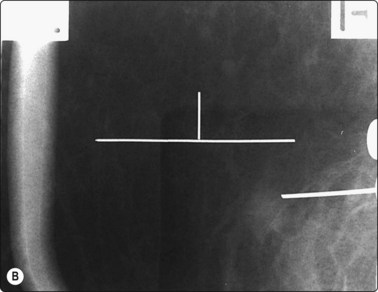

Breast biopsy and carbon marking for localization of clinically occult lesions

Mammographic screening has led to developments in biopsy and localisation of the small, clinically occult lesions detected by these programs. The most useful and common methods are ultrasound with and without a transducer attachment, a stereotactic attachment for upright mammographic X-ray units (Fig. 3.4) or a dedicated prone stereotactic mammographic biopsy table. When combined with FNAB and localization, either with a hookwire or preferably with carbon marking of the track,11 these techniques efficiently provide maximal information for the clinician with the minimum of inconvenience to the patient (Table 3.1).11 There is then the option to proceed to core biopsy if indicated by the FNAB result.

image

Fig. 3.4 Fine needle biopsy of a suspicious tumour mass in a small breast

Continuous visualization of the needle tip prevents the risk of pneumothorax.

Digital stereotactic localization, with either the upright or prone units, shortens the time of the procedure in comparison with a film-screen radiographic technique and gives rapid accurate localization. There are disadvantages to the prone units, particularly in cost and inability to utilize them for other mammographic purposes, and there is some restriction in positioning and access to deep lesions in the breast. These are overcome with some modern upright mammographic units which allow gantry tilt and, with a digital stereotactic attachment, can localize a breast lesion from any projection, including from the inferior aspect, with the patient lying on her side. This mitigates the problem of vasovagal attacks, one of the criticisms of the upright biopsy method. There is also much greater access to the breast with this method.